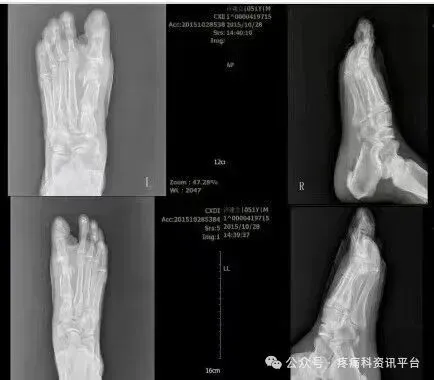

原石家庄市三院副院长冯建书亲自讲课示教,患者身边近距离看手术,可随时提问。冯建书:原石家庄第三医院(石家庄市骨科医院)副院长 手足外科主任可开发票,会后由承办单位石家庄君臣佐使会议服务有限公司提供会务费发票.图为术前术后对比图

本次培训以“理论+临床观摩+学员亲自动手截骨(动物标本)"为主,三位一体全面掌握这项技术。在上午理论授课环节,冯主任亲授临床经验和技巧,共同分享多年临床经验和研究心得,让大家在学习中相互交流,在实践中共同进步。培训间隙,老师会教大家术后包扎要领、手术松解等内容下午安排进手术室观摩,老师边手术边讲解在术中需要注意的地方,通过近距离的观摩深入掌握了解这项技术